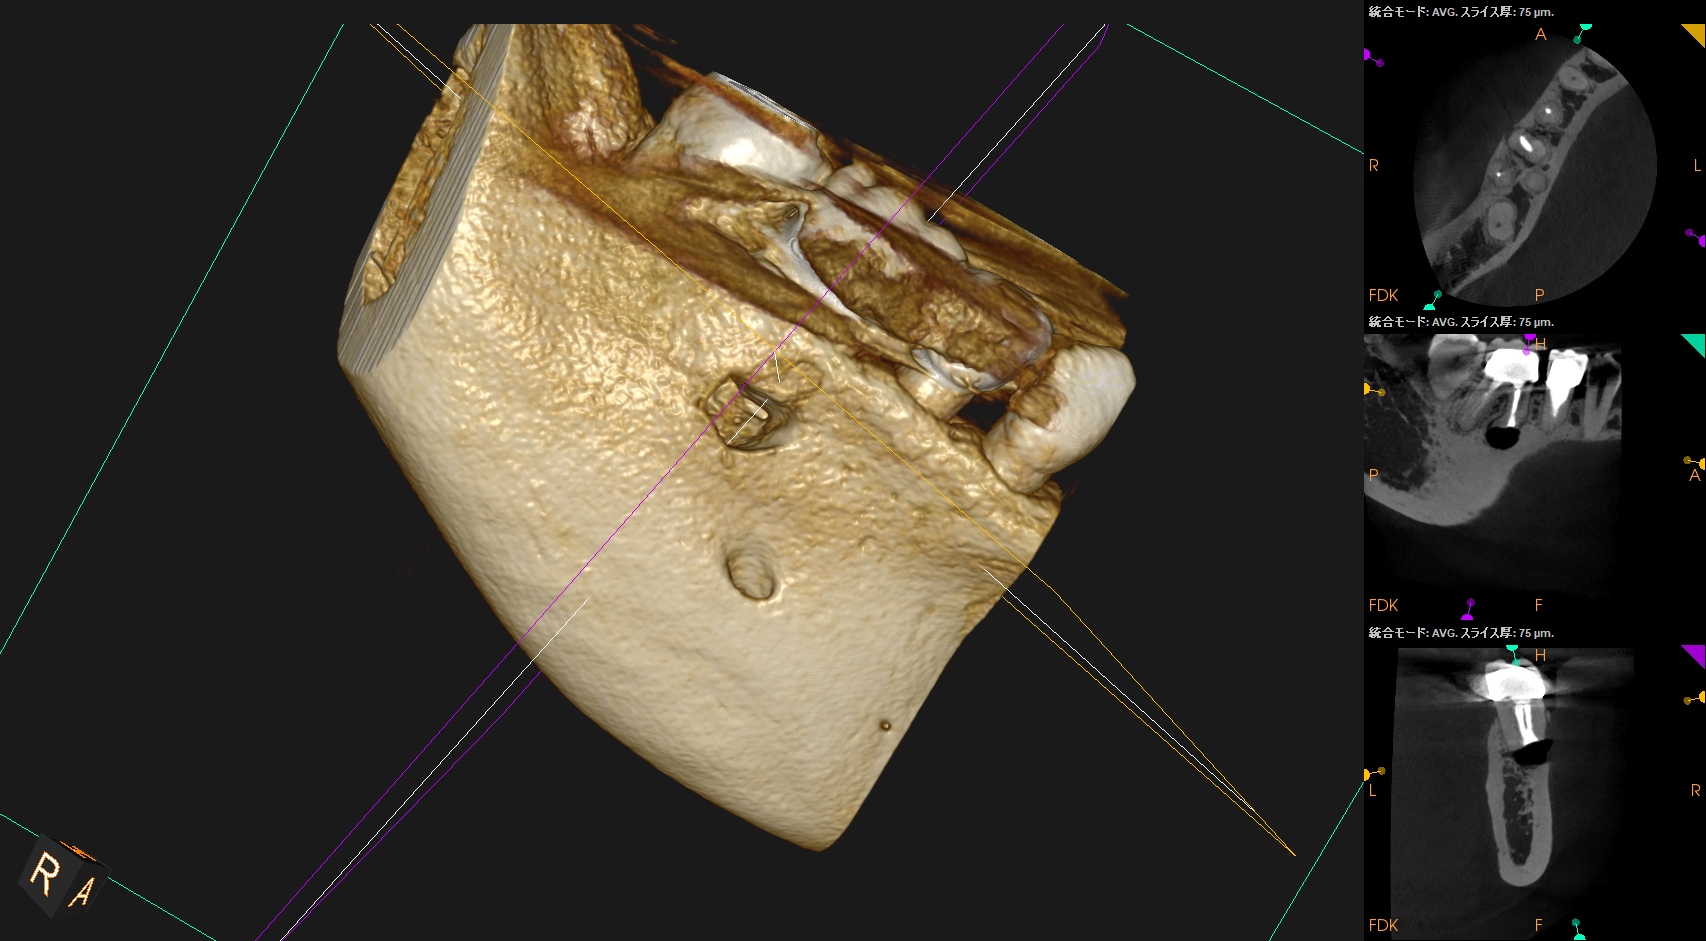

#30 M Apicoectomy 8M recall(2026.2.6)

骨欠損は完治していないが、検査で臨床症状が消失した点と、

術直後が、

骨欠損が今よりも大きく8ヶ月で縮小していることから問題はないと考える。

術直後と比較した。

完治ではないが大幅に問題が解決していることがわかる。